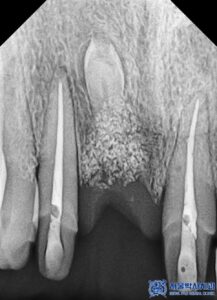

또한 신경치료에서 가장 중요한 것은 치아 내부를

얼마나 깨끗하게 소독하고,

이후 어떤 재료로 신경관을 채우느냐입니다.

대부분의 치과에서는 신경치료 후 신경관을 고무 성분

(가타퍼차, Gutta-Percha)으로

충전하는 방식으로 마무리합니다.

하지만 서울박사치과에서는

더욱 철저한 치료를 위해 MTA

(바이오세라믹 재료)를 사용합니다.